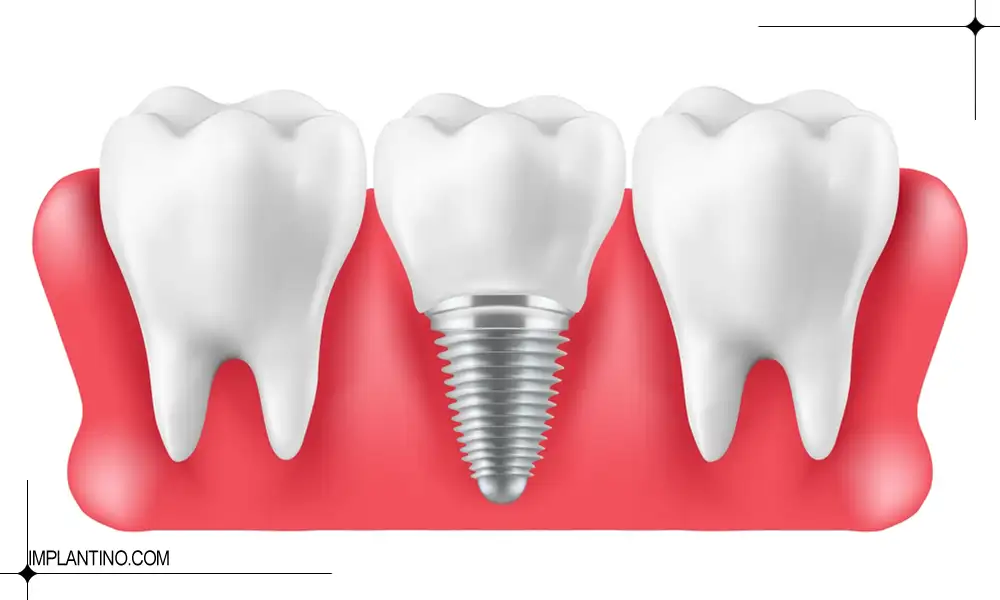

ترمیم ایمپلنت دندان به معنای اصلاح بخش های آسیب دیده مانند روکش، اباتمنت (اتصال دهنده ایمپلنت و روکش) یا حتی بافت لثه اطراف ایمپلنت است. این ترمیم می تواند شامل تعویض روکش ایمپلنت شکسته، سفت کردن پیچ لق شده یا درمان التهاب لثه اطراف ایمپلنت باشد.

| سفت کردن یا تعویض پیچ و اباتمنت | در صورت لق شدن پیچ یا اباتمنت، دندانپزشک آن را سفت کرده یا تعویض می کند تا ایمپلنت پایدار شود. |

اولین قدم در ترمیم ایمپلنت شکسته، ارزیابی شدت آسیب است. در صورتی که شکستگی محدود به تاج یا روکش ایمپلنت باشد، دندانپزشک معمولاً با تعویض یا بازسازی روکش، ظاهر و عملکرد ایمپلنت را باز می گرداند. اگر آسیب به پیچ یا اباتمنت وارد شده باشد، سفت کردن، تعویض یا اصلاح آن لازم است تا ثبات ایمپلنت حفظ شود.